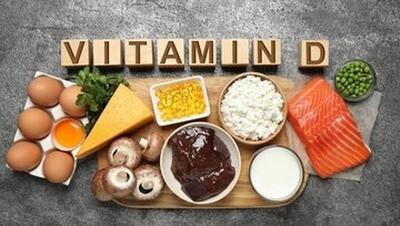

اندیشه معاصر- آنچه که از مصرف ویتامین D نمی دانید اندیشه معاصر

یک عضو هیئت علمی دانشگاه علوم پزشکی اصفهان، گفت: افرادی که دچار چاقی و اضافه وزن هستند بیشتر در معرض کمبود ویتامین D قرار دارند. همچنین، کم تحرکی میتواند مانع جذب ویتامین D در بدن شود.